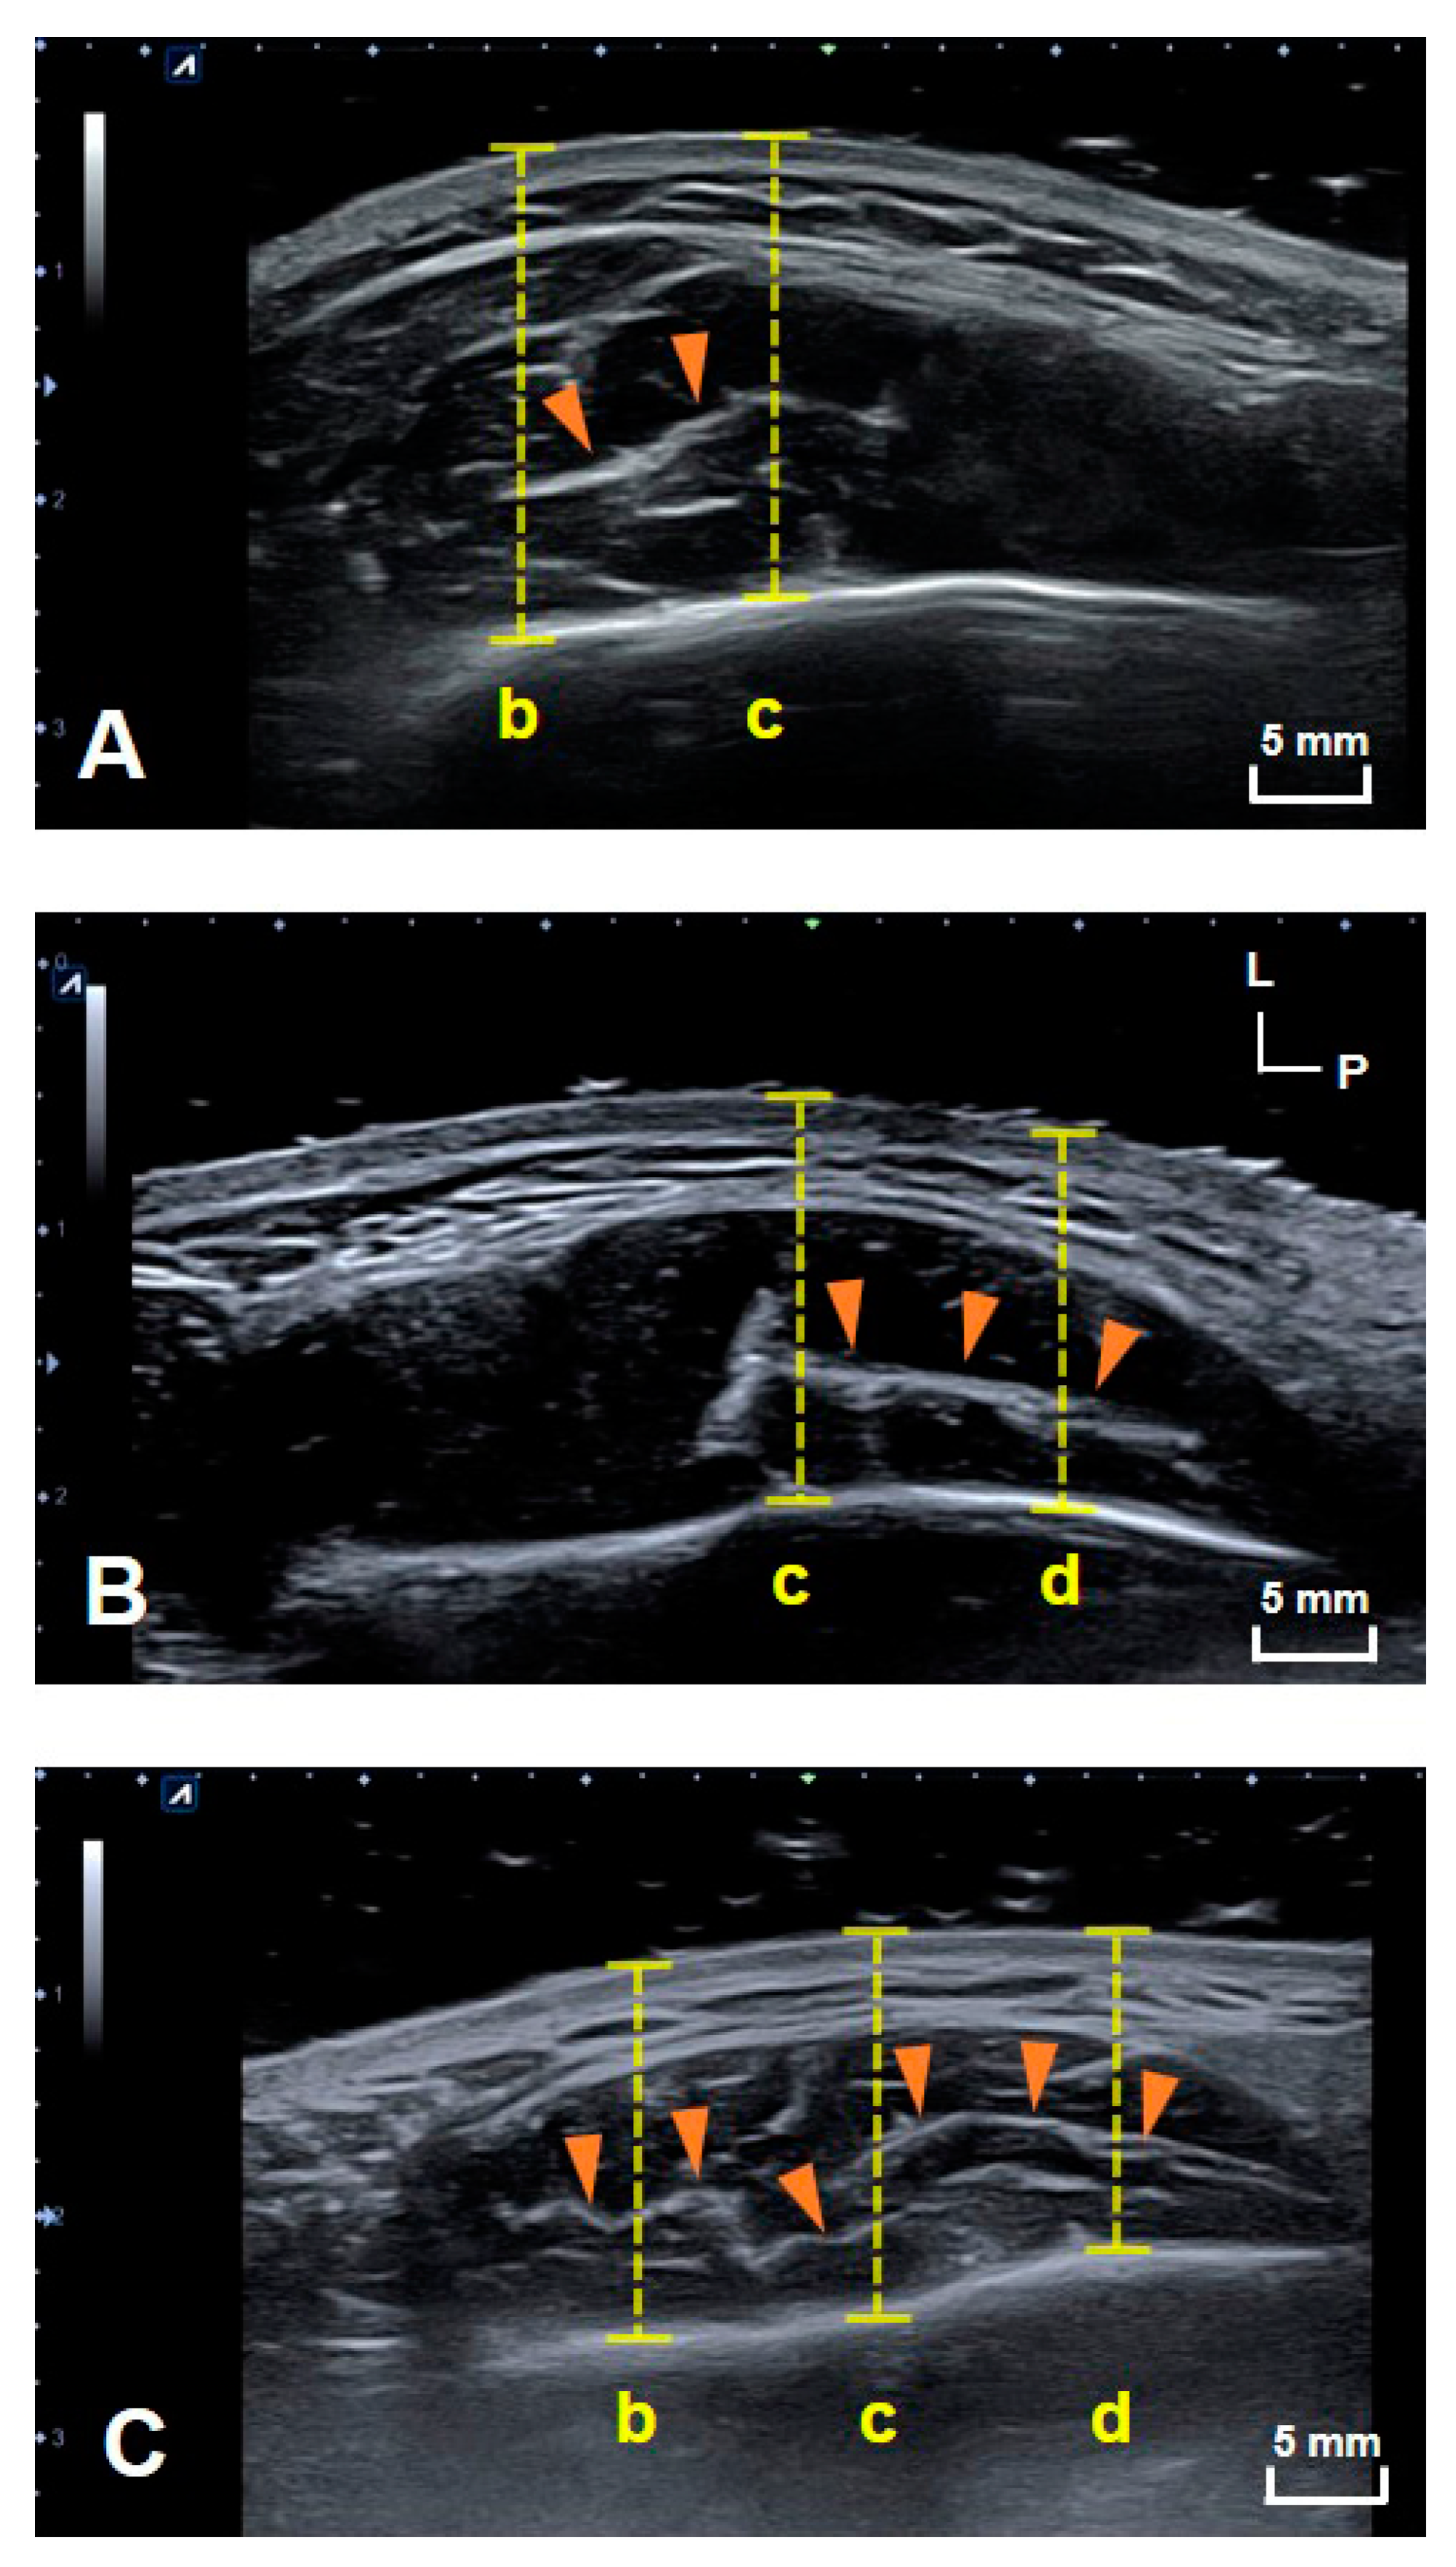

US images of the DIT of the masseter muscle were obtained in all subjects on both sides. The structural patterns of the DIT were classified into three different types. Type A covered reference lines b and c (anterior two-thirds of the masseter muscle); type B covered reference lines c and d (posterior two-thirds of the masseter muscle); and type C covered reference lines b, c and d (most of the inferior part of the masseter muscle). Figure 1 shows example images of DITs with structural patterns of types A (21.8%, n = 7), B (9.4%, n = 3) and C (68.8%, n = 22). The DIT could be detected more easily on longitudinal images than transverse images. The classification into the three tendon types did not differ significantly with sex, age, or left and right sides.

Figure 1.

Transverse US images showing the three patterns of the DIT. US images of (A) types A, (B) B and (C) C. (b) The line halfway between the anterior border of the masseter muscle and line c, (c) the line halfway between the anterior and posterior borders of the masseter muscle, and (d) the line halfway between line c and posterior border of the masseter muscle. The yellow dashed lines indicate the depth from the skin surface to the mandible. L, lateral; P, posterior; orange arrowheads, DIT.

The present study used US to verify the structural patterns of the DIT of the masseter muscle in healthy young volunteers and compared the findings with those obtained in previous cadaver dissections. Performing US scanning at the same sites as in the cadaveric study has clearly revealed the structural patterns of the DIT. Furthermore, the structural pattern of the DIT was classified into three types: Type A covered references lines b and c (anterior two-thirds of the masseter muscle); type B covered reference lines c and d (posterior two-thirds of the masseter muscle); and type C covered reference lines b, c and d (most of the inferior part of the masseter muscle) (Figure 1).